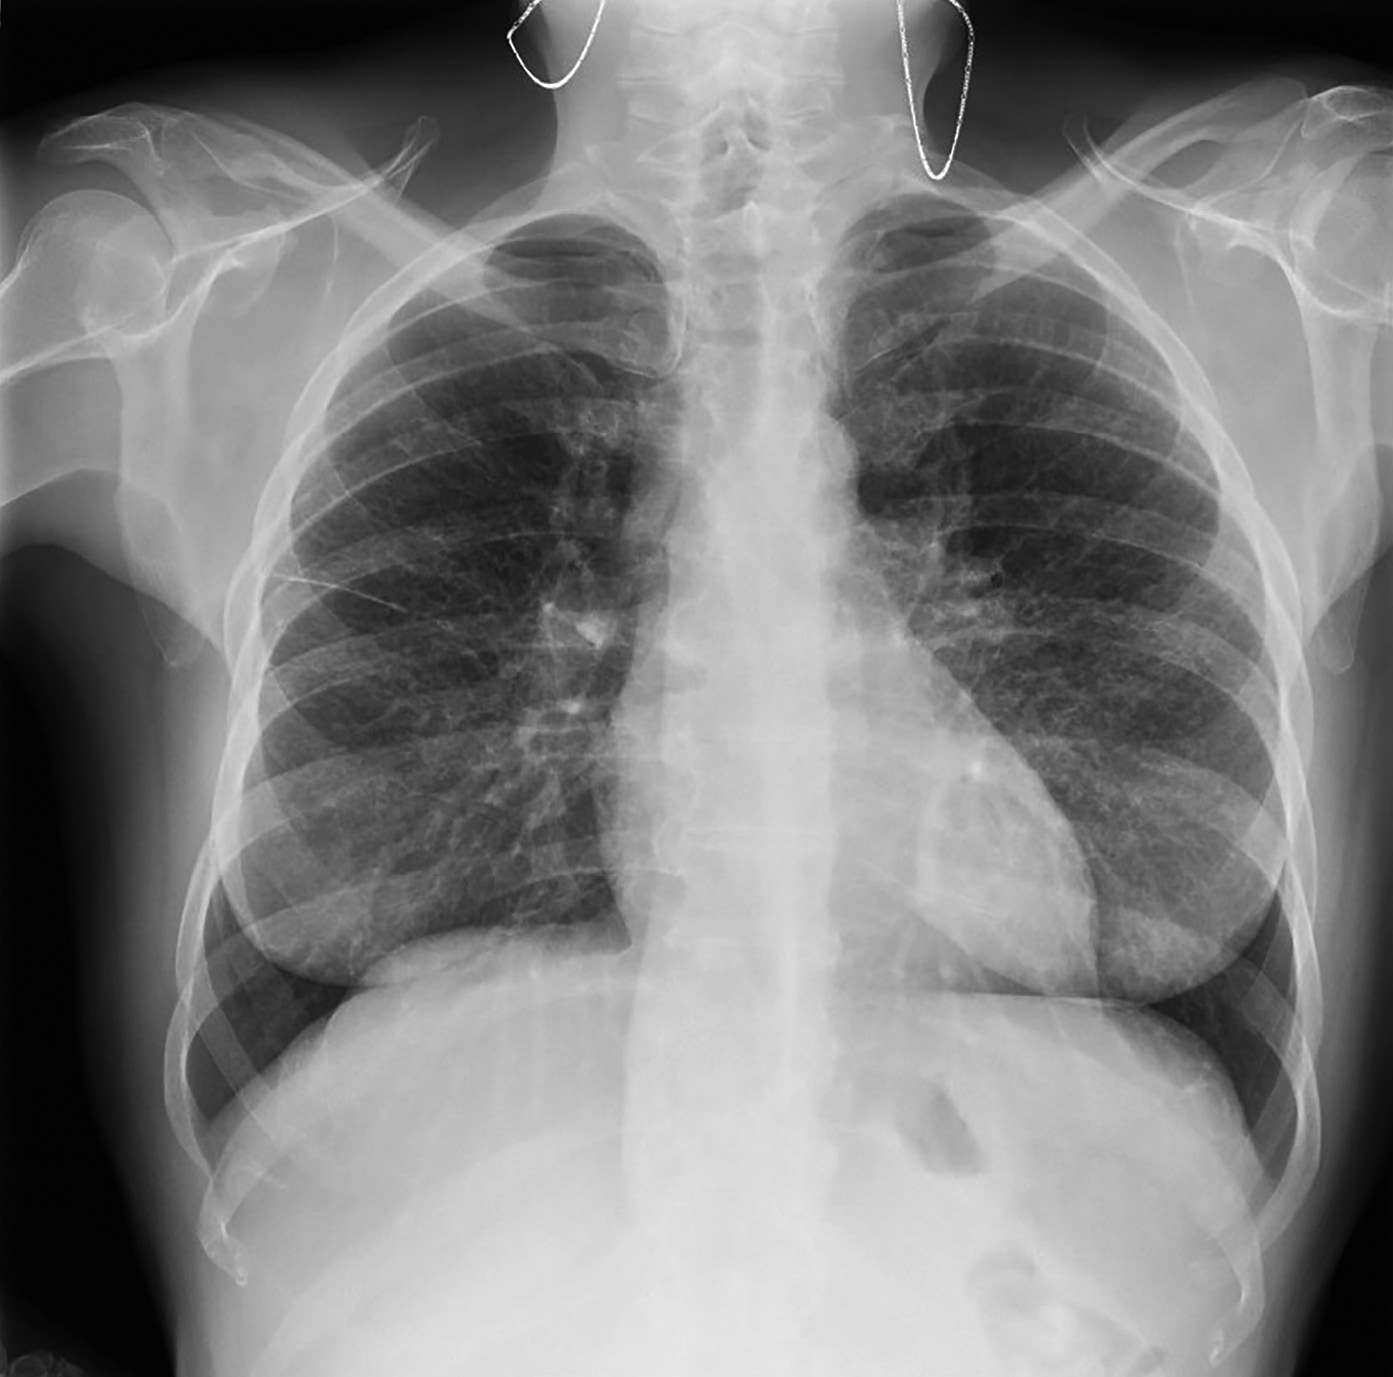

В 2017 г. (в 45 лет) при обследовании по поводу длительно непроходящего кашля выявлен саркоидоз легких и внутригрудных лимфатических узлов. По данным рентгенографии легких от 08.2023 г. (рис. 4), легкие умеренно эмфизематозны, корни расширены, фиброзны, бронхолегочный рисунок деформирован, усилен по интерстициально-сосудистому типу, имеется увеличение внутригрудных лимфатических узлов. Междолевая шварта справа. Со слов пациентки, она была консультирована пульмонологом, морфологическая верификация диагноза не требуется.

Рисунок 4. Рентенография легких пациентки Д.